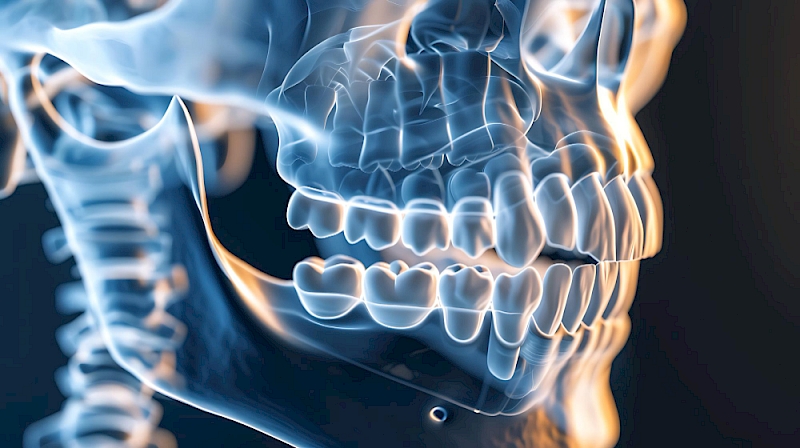

Orthognatic Surgery

Orthognathic surgery is a treatment option that aims to correct the skeletal structure and deformities of the jaws and the relationship between the jaw and face performed by a plastic surgeon or maxillofacial surgeon under general anesthesia.